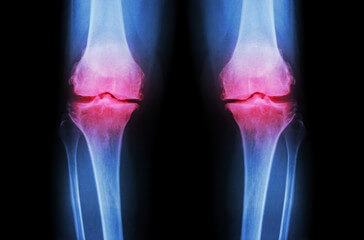

퇴행성 관절염

무릎을 장시간 사용하게 되면 연골이 약해져 벗겨질 수 있습니다. 그런 경우 관절이 매우 부드럽게 움직여야 하는데 거칠게 움직이면 삼출액이 차면서 고이게 됩니다. 경미한 퇴행성 관절염의 경우 활액의 양은 정상과 거의 같지만 증상이 심해지면 활액의 양이 3배 정도 늘어나 통증이 동반됩니다.

이 경우 물기를 제거하고 증상을 개선해도 거친 표면 자체가 해결되지 않으면 걸을 때마다 자극이 발생하여 다시 물이 차게 됩니다.

증상이 진행됨에 따라 무릎에 심한 통증이 지속되고 다리가 휘는 등의 관절 변형이 나타나며 보행장애가 나타나 일상생활에 지장이 크므로 인공관절치환술 등의 수술적 치료를 진행한다고 합니다.